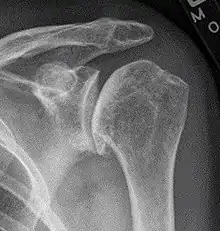

X-ray of shoulder osteoarthritis.

Arthritis of the shoulder causes pain and loss of motion and use of the shoulder. X-rays of the shoulder show loss of the normal space between the ball and socket. X-ray can provide radiographic staging of shoulder osteoarthritis.